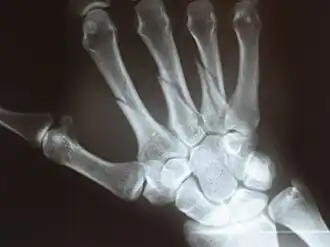

Пястные кости (лат. ossa metacarpi) — пять коротких трубчатых костей кисти, лучами отходящих от запястья. Нумерация пястных костей соответствует нумерации сочленяющихся с ними пальцев. В пястных костях различают основание (лат. basis), тело (лат. corpus) и головку (лат. caput).

Утолщенный проксимальный конец пястной кости называется её основанием. Пястная кость сочленена как с дистальным рядом костей запястья, так и с соседними пястными костями. Тело пястной кости (её основная часть) имеет несколько изогнутую к тылу форму, содержит питательный канал (лат. canalis nutricius), открывающийся с ладонной стороны кости питательным отверстием (лат. foramen nutricium). Головка (дистальный эпифиз) пястной кости шаровидная, её суставная поверхность несколько возвышена с ладонной стороны.